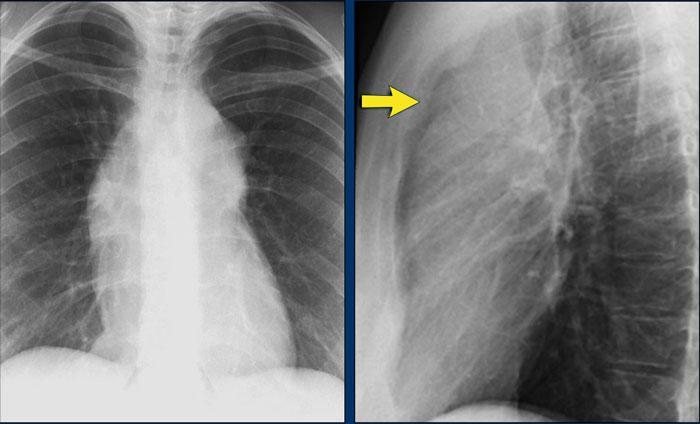

Một mặt tiếp giáp trung thất–phổi quan trọng cần đánh giá là ngách tĩnh mạch đơn–thực quản (mũi tên vàng).

Ngách tĩnh mạch đơn–thực quản

Lệch đường tĩnh mạch đơn–thực quản có thể do:

- Thoát vị khe thực quản

- Bệnh lý thực quản

- Giãn nhĩ trái

- Hạch to dưới carina

- Nang phế quản

Trên phim X-quang ngực tư thế PA, có thể thấy đường tĩnh mạch đơn–thực quản bị lệch sang bên.

Nguyên nhân là do thoát vị khe thực quản.

Mũi tên chỉ vào thuốc cản quang barium trong túi thoát vị khe thực quản.